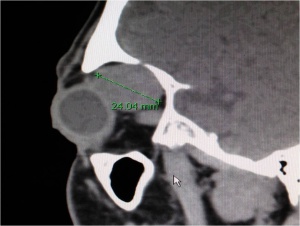

CT scan of the orbits with contrast enhancement is the radiologic study of choice for the diagnosis of PALG. Thin sections through the orbits highlight bony tissue which is critical in differentiating PALG from ACC. Features of PALG on CT include: solid (can be heterogenous), well defined, round or oval, occasional calcification, and bony remodeling (see figures 5-7). In contrast, ACC typically features: irregular margins (although can be well circumscribed), nodularity (with infiltration of adjacent tissue), calcification, and bony destruction.[6]